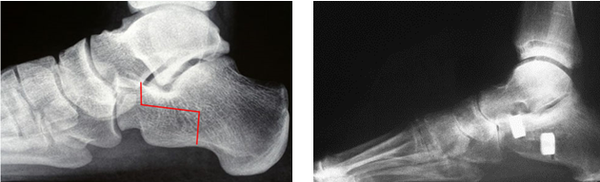

Rotational calcaneal osteotomy

This procedure combines some of the advantages of the Evans and the MDCO providing an increased ability to realign severe mal-alignment without fusing any joints.

There remains the risk in the adult patient of developing arthritis in other foot joints, depending on how well the individual adapts to the foot being repositioned. Other risks include nerve and tendon irritation due to the increased dissection and the proximity of these structures.

(Pre and post X-rays showing the line of the bone cuts and subsequently view post procedure with the calcaneum lengthened and rotated at the same time)